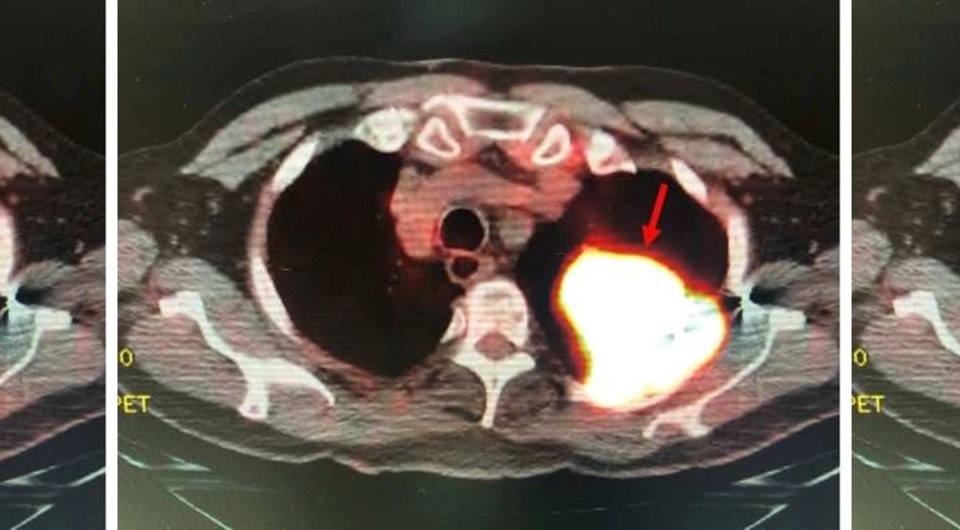

Позитронно-эмиссионная томография выявила изолированное образование в левой верхней доле легкого с локальным поражением грудной стенки без признаков метастазирования. Биопсия легкого подтвердила диагноз мелкоклеточного рака легкого. Врачи удалили пораженную долю легкого вместе с регионарными лимфоузлами.

Гистологическое исследование выявило низкодифференцированную мелкоклеточную карциному с четкими хирургическими границами. Кроме того, в опухоли обнаружили фрагменты свинцовой пули. В дальнейшем пациент прошел курс химиотерапии и радиотерапии и через три года после операции продолжал чувствовать себя хорошо, а врачи не обнаружили признаков рецидива.